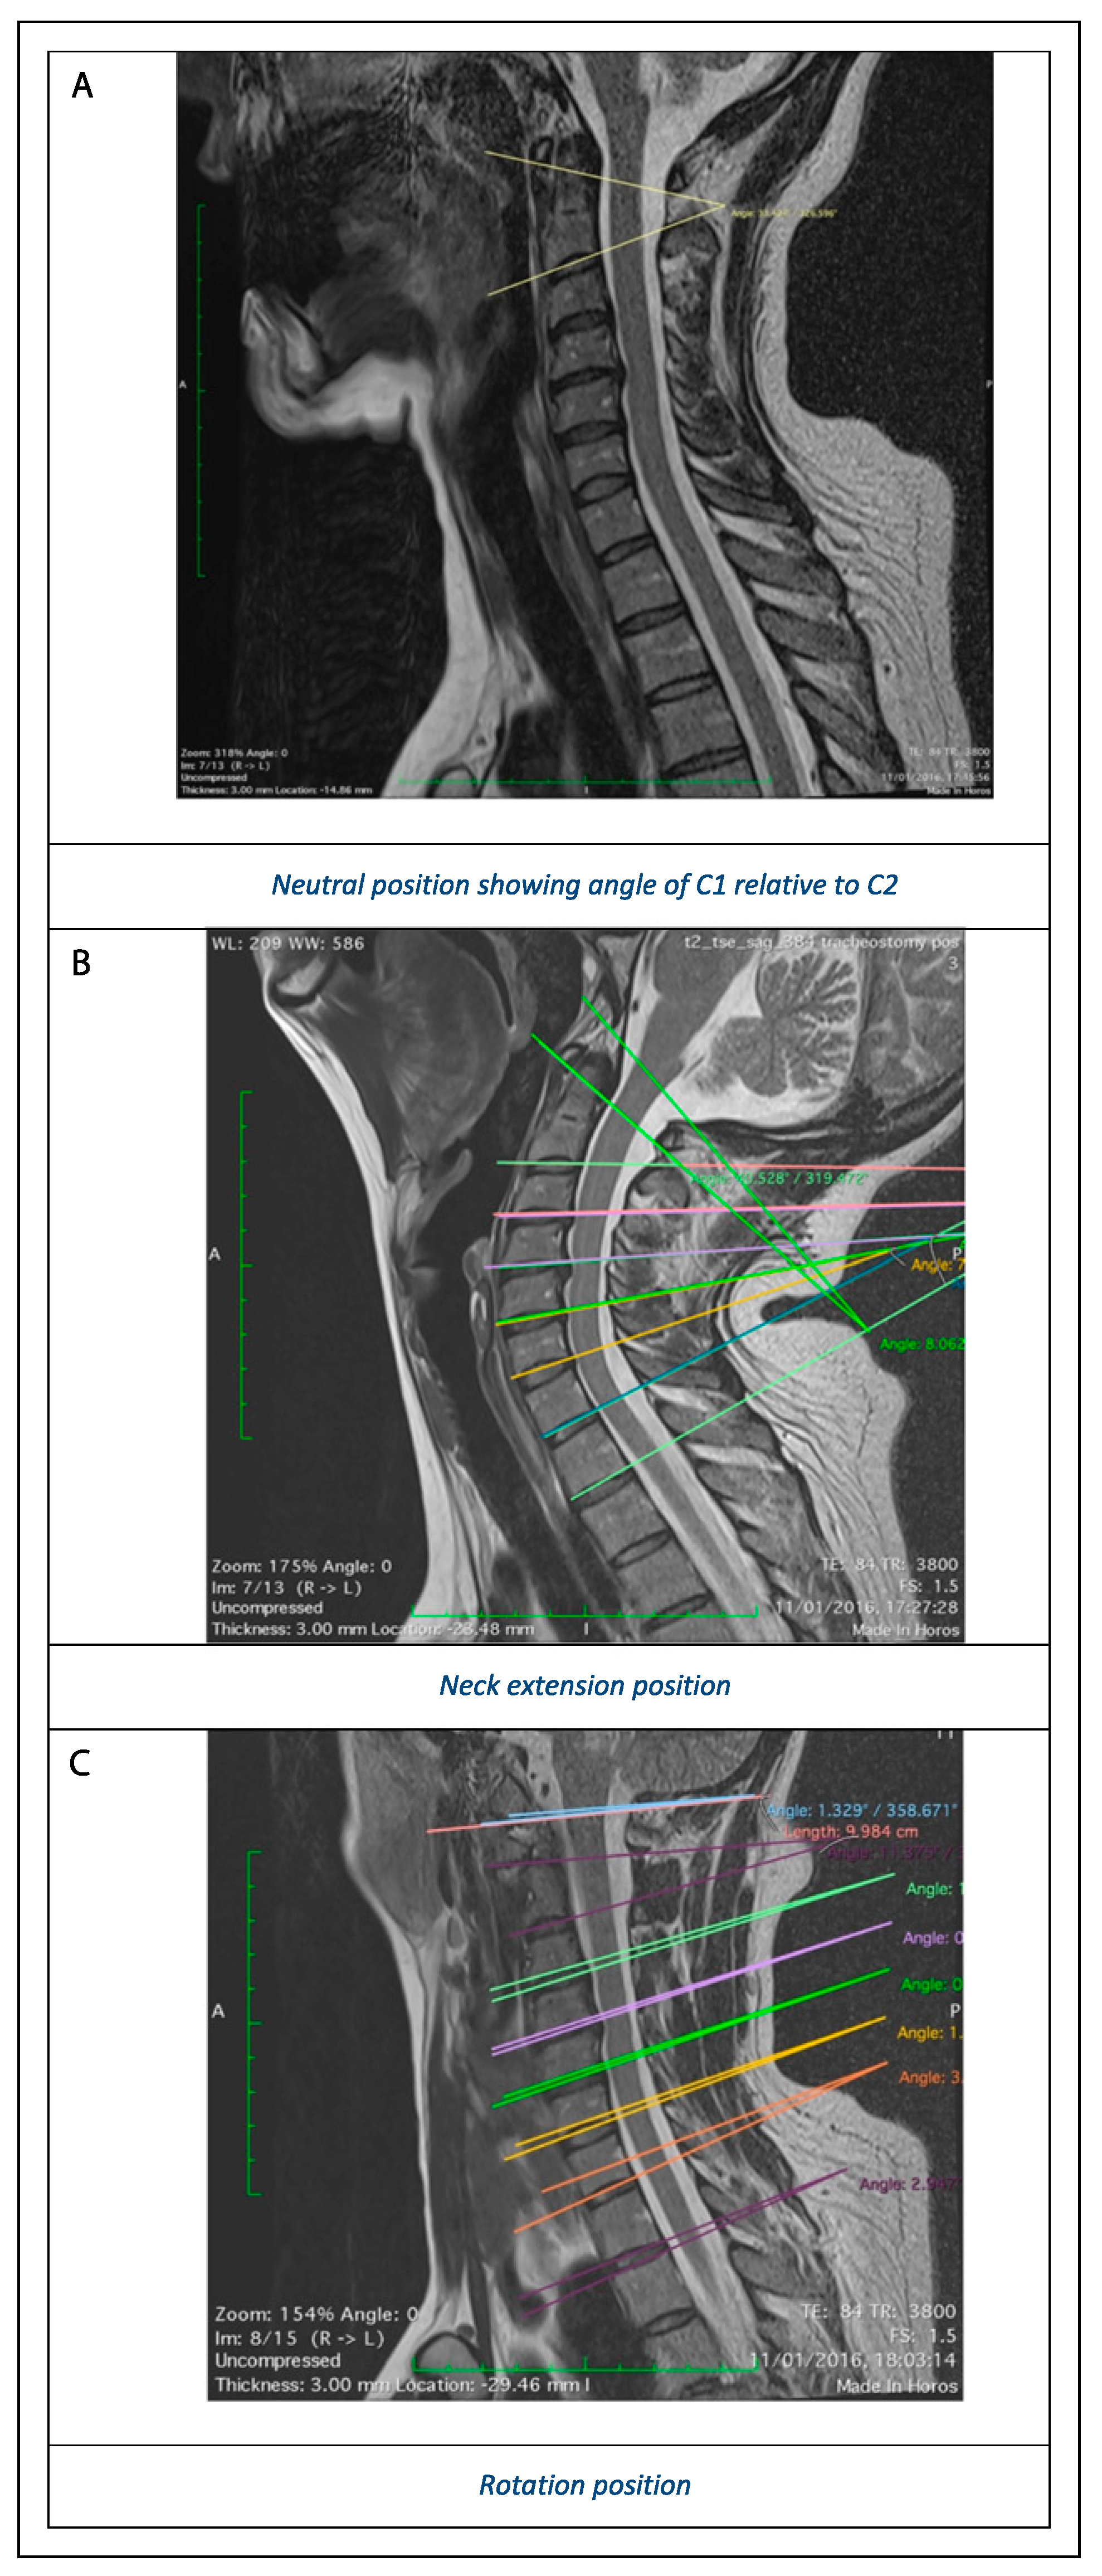

The effect of C-spine manipulation on different vertebral levels was evaluated by calculating the angle (in degrees) of the axes of each vertebra on the level below, in all three surgical positions. This was performed using an electronic protractor on the sagittal images for AP flexion/extension (Figure 1) and the axial images for lateral rotation. AP flexion/extension was calculated at each vertebral level, as the ‘sagittal intervertebral angle’ made between the inferior vertebral endplate and a similar line at the level below (Figure 2a–c). Rotation was calculated on axial images the ‘transverse intervertebral angle’, made by a line traversing the midpoint of the vertebral body plus spinous process at each level compared with the level below. At the skull base, these angles were defined by the line connecting basion to opisthion (anterior and posterior margins of foramen magnum) relative to the line traversing inferior margin of C1. All image analysis was performed in OsiriX (Pixmeo, Geneva, Switzerland).

Images showing gross spinal alignment during intraoperative simulation are shown in Figure 1 and Figure 2.

Figure 2. (a) Neutral position showing angle of C1 relative to C2. (b) Neck extension position. (c) Rotation position.